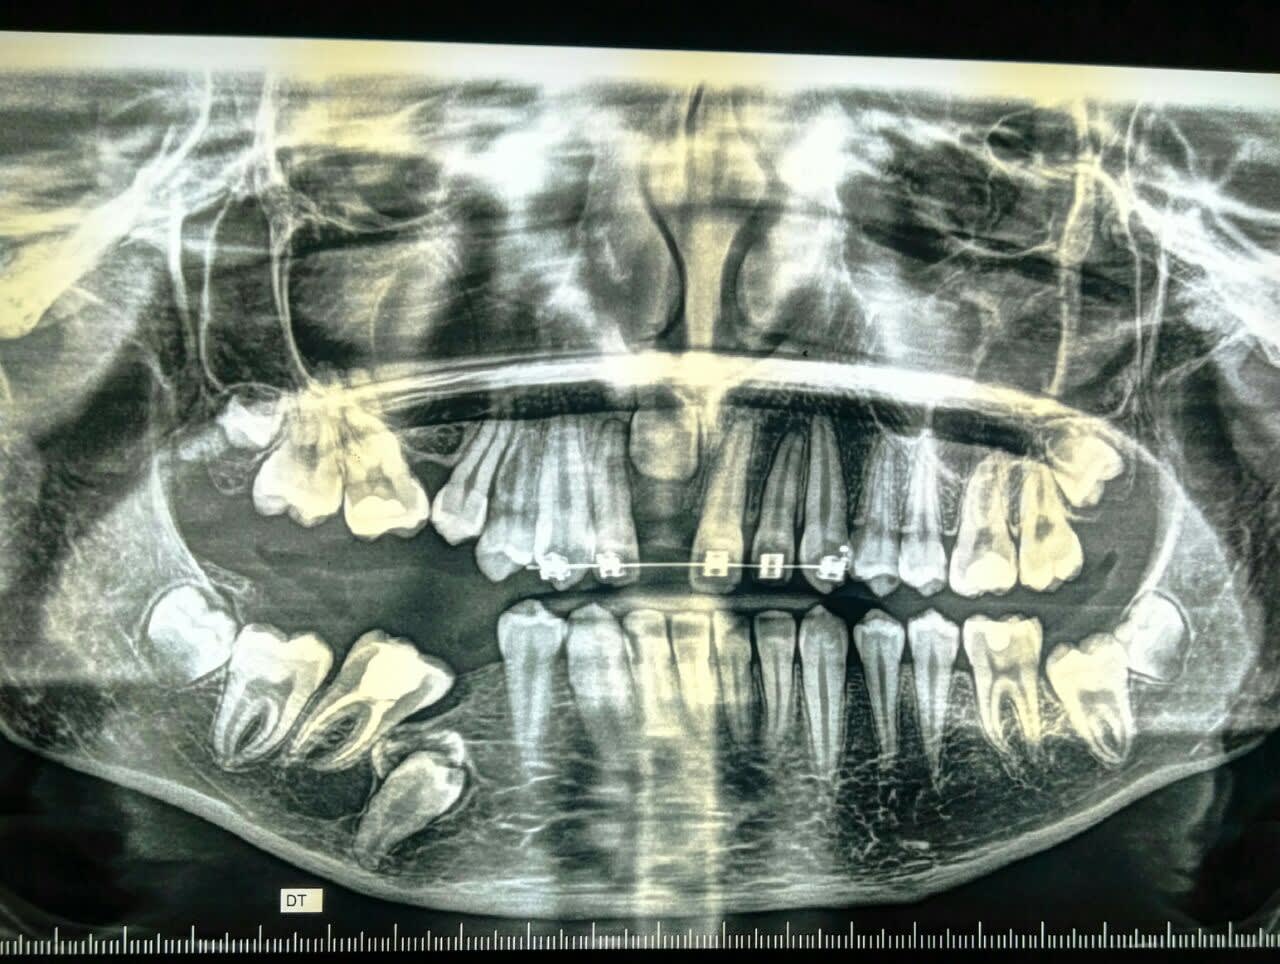

Un confrère m'a envoyé ces photos ( panoramique et téléradiographie) pour avis.

Une reprise d'un traitement orthodontique !

Mon avis:

- Cône Beam

- si les racines des dents incluses n'ont pas terminées leurs évolution, il faudra les extraire et prévoir des implants après correction orthodontique des deux arcades.

Si au contraire les racines sont bien évoluées alors il faudra les faire intégrer dans le plan de traitement orthodontique.

Sinon cela mise à part et avant de critiquer celui qui à commencer le traitement je remarque :

- bracket seulement en anterieur au maxillaire sup

- grosse béance postérieur à droite due à la fois au secteur 1 et 4 . Je n'aime pas du tout les asymmetrie

- 45 ankylosé ( là pas de gros doute )

Conclusion :

Défaut d'éruption asymétrique, , je chercherais du coté d'un syndrome. Perso c'est le genre de cas ou je consulterais le département orthodontique d'une fac.

Cas pluridiscplinaire qui vas demander au niveau de l'ortho une mécanique non classique dans tout les cas, avec probablement de la chir associé.